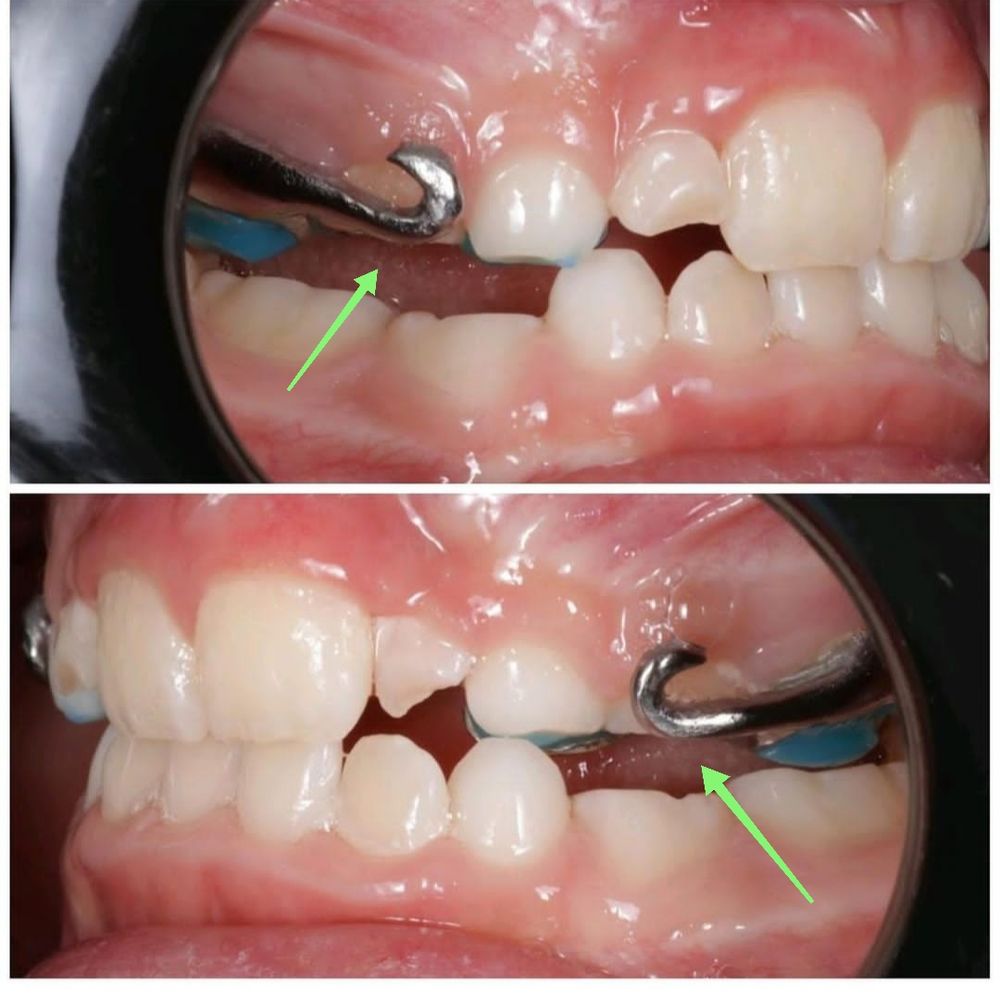

Ксюша, посмотрите, пожалуйста. Добавила фото.

Secrets_of_the_rain, у нас их не было🤷🏼‍♀️ десна вряд ли привыкнет, я бы записывалась к ортодонту на коррекцию Изображение

Ксюша, у нас их, видимо, добавили для ношения лицевой маски, чтобы нижняя челюсть не заходила на верхнюю. Я сама сейчас только увидела. Вот и думаю, что к такому вряд ли можно привыкнуть(((. Спасибо за ответ!

VER4EVI4, я просто боюсь, что крючки как-то так сделаны, что натирают десну и к этому нельзя будет привыкнуть. На остальные части аппарата жалоб нет. Именно на боль в дёснах, где соприкасаются крючки. У вас аппарат с крючками был или без?